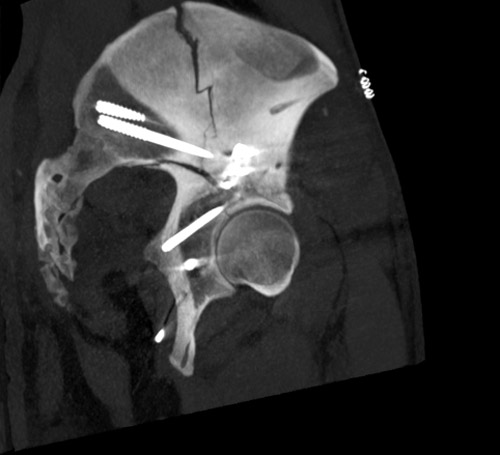

Emergency CT-scan with overthigthened binder

Emergency CT scan